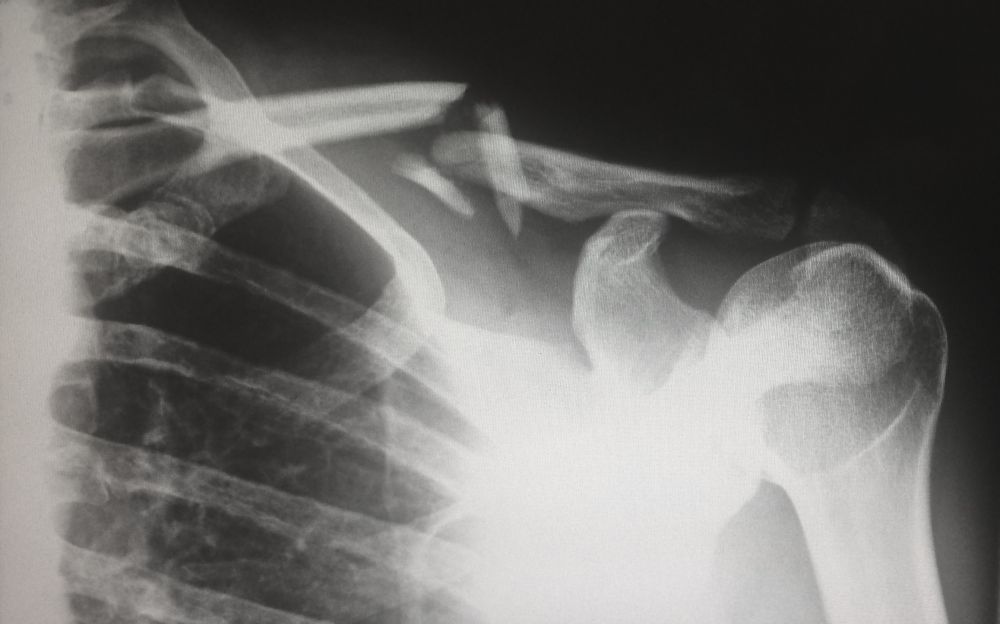

ultralydundersøgelse